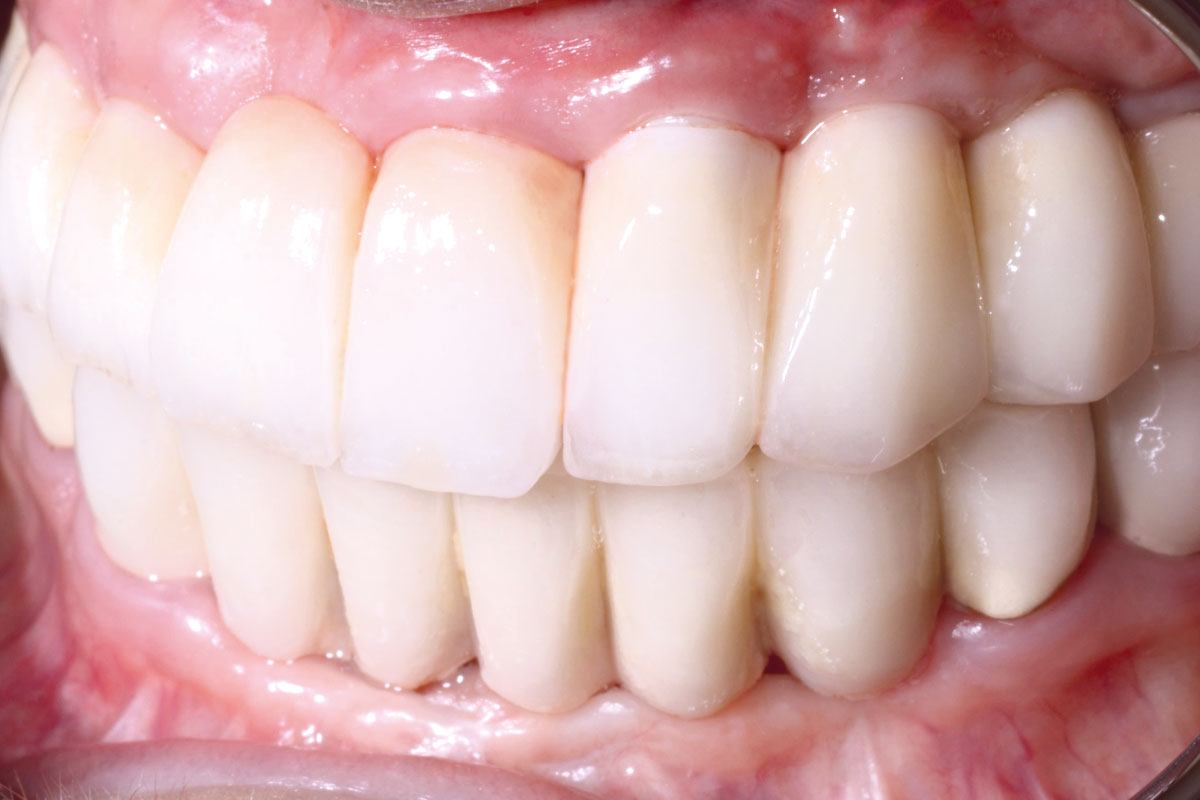

14/16 - Prosthetic work

Reconstruction of Anterior Maxilla with maxgraft® bonebuilder – Dr. B. Han